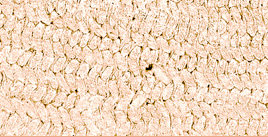

Another way to learn about Chalky Molars is to do "Lots Of Looking" with Special Machines. Some of the machines are called Microscopes. They work like Magnifying Glasses to make small things really big. Other machines grind the teeth into thin slices or dust, and then make pictures of their ingredients. All these Experiments let Scientists see what is different about Chalky Teeth. On the Right you can see three different pictures made with Normal and Wonky Teeth. If you want to see the Special Machine that made the picture, and the Tooth Scientist that used the machine, then click on each picture or use the link below.